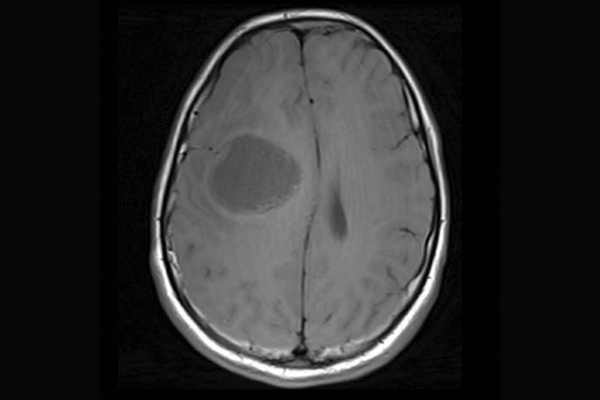

A scan of a brain with priMMRD subtype 1

priMMRD-3: The immune-cold

Accounting for the remaining 19 per cent of gliomas studied, these tumours have MMRD mutations and a variation in the IDH1 gene. While they often have poor responses to immunotherapy alone, SickKids clinicians and scientists are working toward a clinical trial to pair targeted immunotherapies with a IDH1 inhibitor to provide more tailored care for this subgroup of patients.